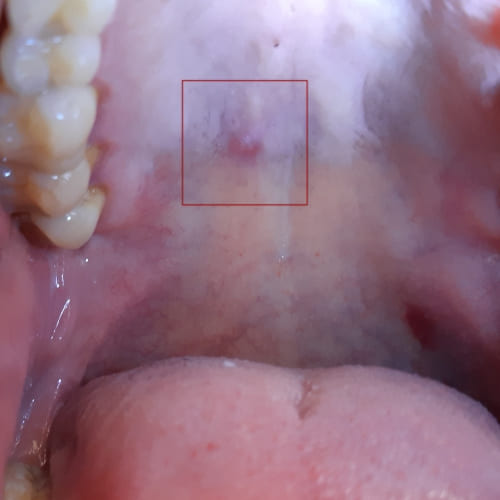

Eine Speicheldrüsenentzündung ist eine Entzündung der großen Speicheldrüsen (auf einer oder beiden Seite) und führt zu einer schmerzhaften Schwellung. Eine Speicheldrüsenentzündung wird durch Bakterien oder Viren verursacht und entwickelt sich sehr schnell.

Die Haut rund um die Speicheldrüsen erscheint oft als gerötet und geschwollen.